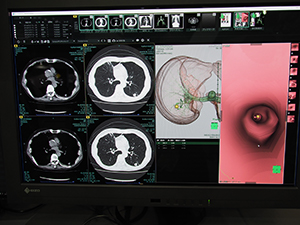

ITソリューションコーナーでは,アーキテクチャを一新した新世代PACSとして昨年のITEM2016で紹介された「SYNAPSE 5(ファイブ)」や3Dワークステーションの「SYNAPSE VINCENT」の次バージョン(version 5)の新機能を中心に展示を構成した。

SYNAPSE 5は,システムのアーキテクチャから一新してサーバサイドレンダリング方式を採用し,大容量の画像データを扱うためにさらなる高速化を図り,PC端末だけでなくタブレット端末などマルチプラットフォームの運用が可能なシステムとなっている。今年のブースでは,SYNAPSE VINCENTとの親和性を高めPACSビューワのフレーム内に画面を表示できることなど,さらに機能を強化したことをアピールした。

そのSYNAPSE VINCENTは,近く登場予定の次バージョンであるversion5に搭載予定の新しい機能を中心に,多くの端末を用意して来場者に紹介した。

その一つが,救急などにおける外傷の緊急止血として行われるけ塞栓術をサポートする“IVRシミュレーター”である。搬送時に撮影された全身CTのデータを基に,カテーテルの経路をシミュレーションして短時間で正確な手技を支援する。SYNAPSE VINCENTでは,画像認識技術によって大血管から末梢血管までを自動で抽出し,さらに血管分岐の方向(角度)を色分けで示し,2次元でのモニタ上でもカテーテルを進める方向をわかりやすく示すことができる。

SYNAPSE 5ではSYNAPSE VINCENTとの連携などを強化 |

SYNAPSE VINCENT v5の新機能“IVRシミュレーター” |